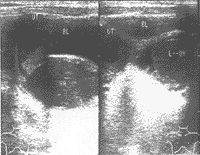

阴道横隔较常见的女性生殖器官先天发育畸形。阴道横隔是指在胚胎期由泌尿生殖窦——阴道球向头端增生、增长演变而成的阴道板,自下而上腔道化时受阻,阴道横隔未贯通或未完全腔化所致。阴道横隔分为完全性横隔和不完全横隔,不完全性横隔多无症状,完全性横隔表现为原发性闭经伴进行性加剧的周期性腹痛,少数伴有泌尿系统和其他器官的异常。阴道横隔的主要治疗方法是手术切除横隔。阴道横隔易形成阴道或宫腔内经血[zhū]留。预后与多方面因素有关,术后若受孕分娩不能顺利进行,需采取剖宫产